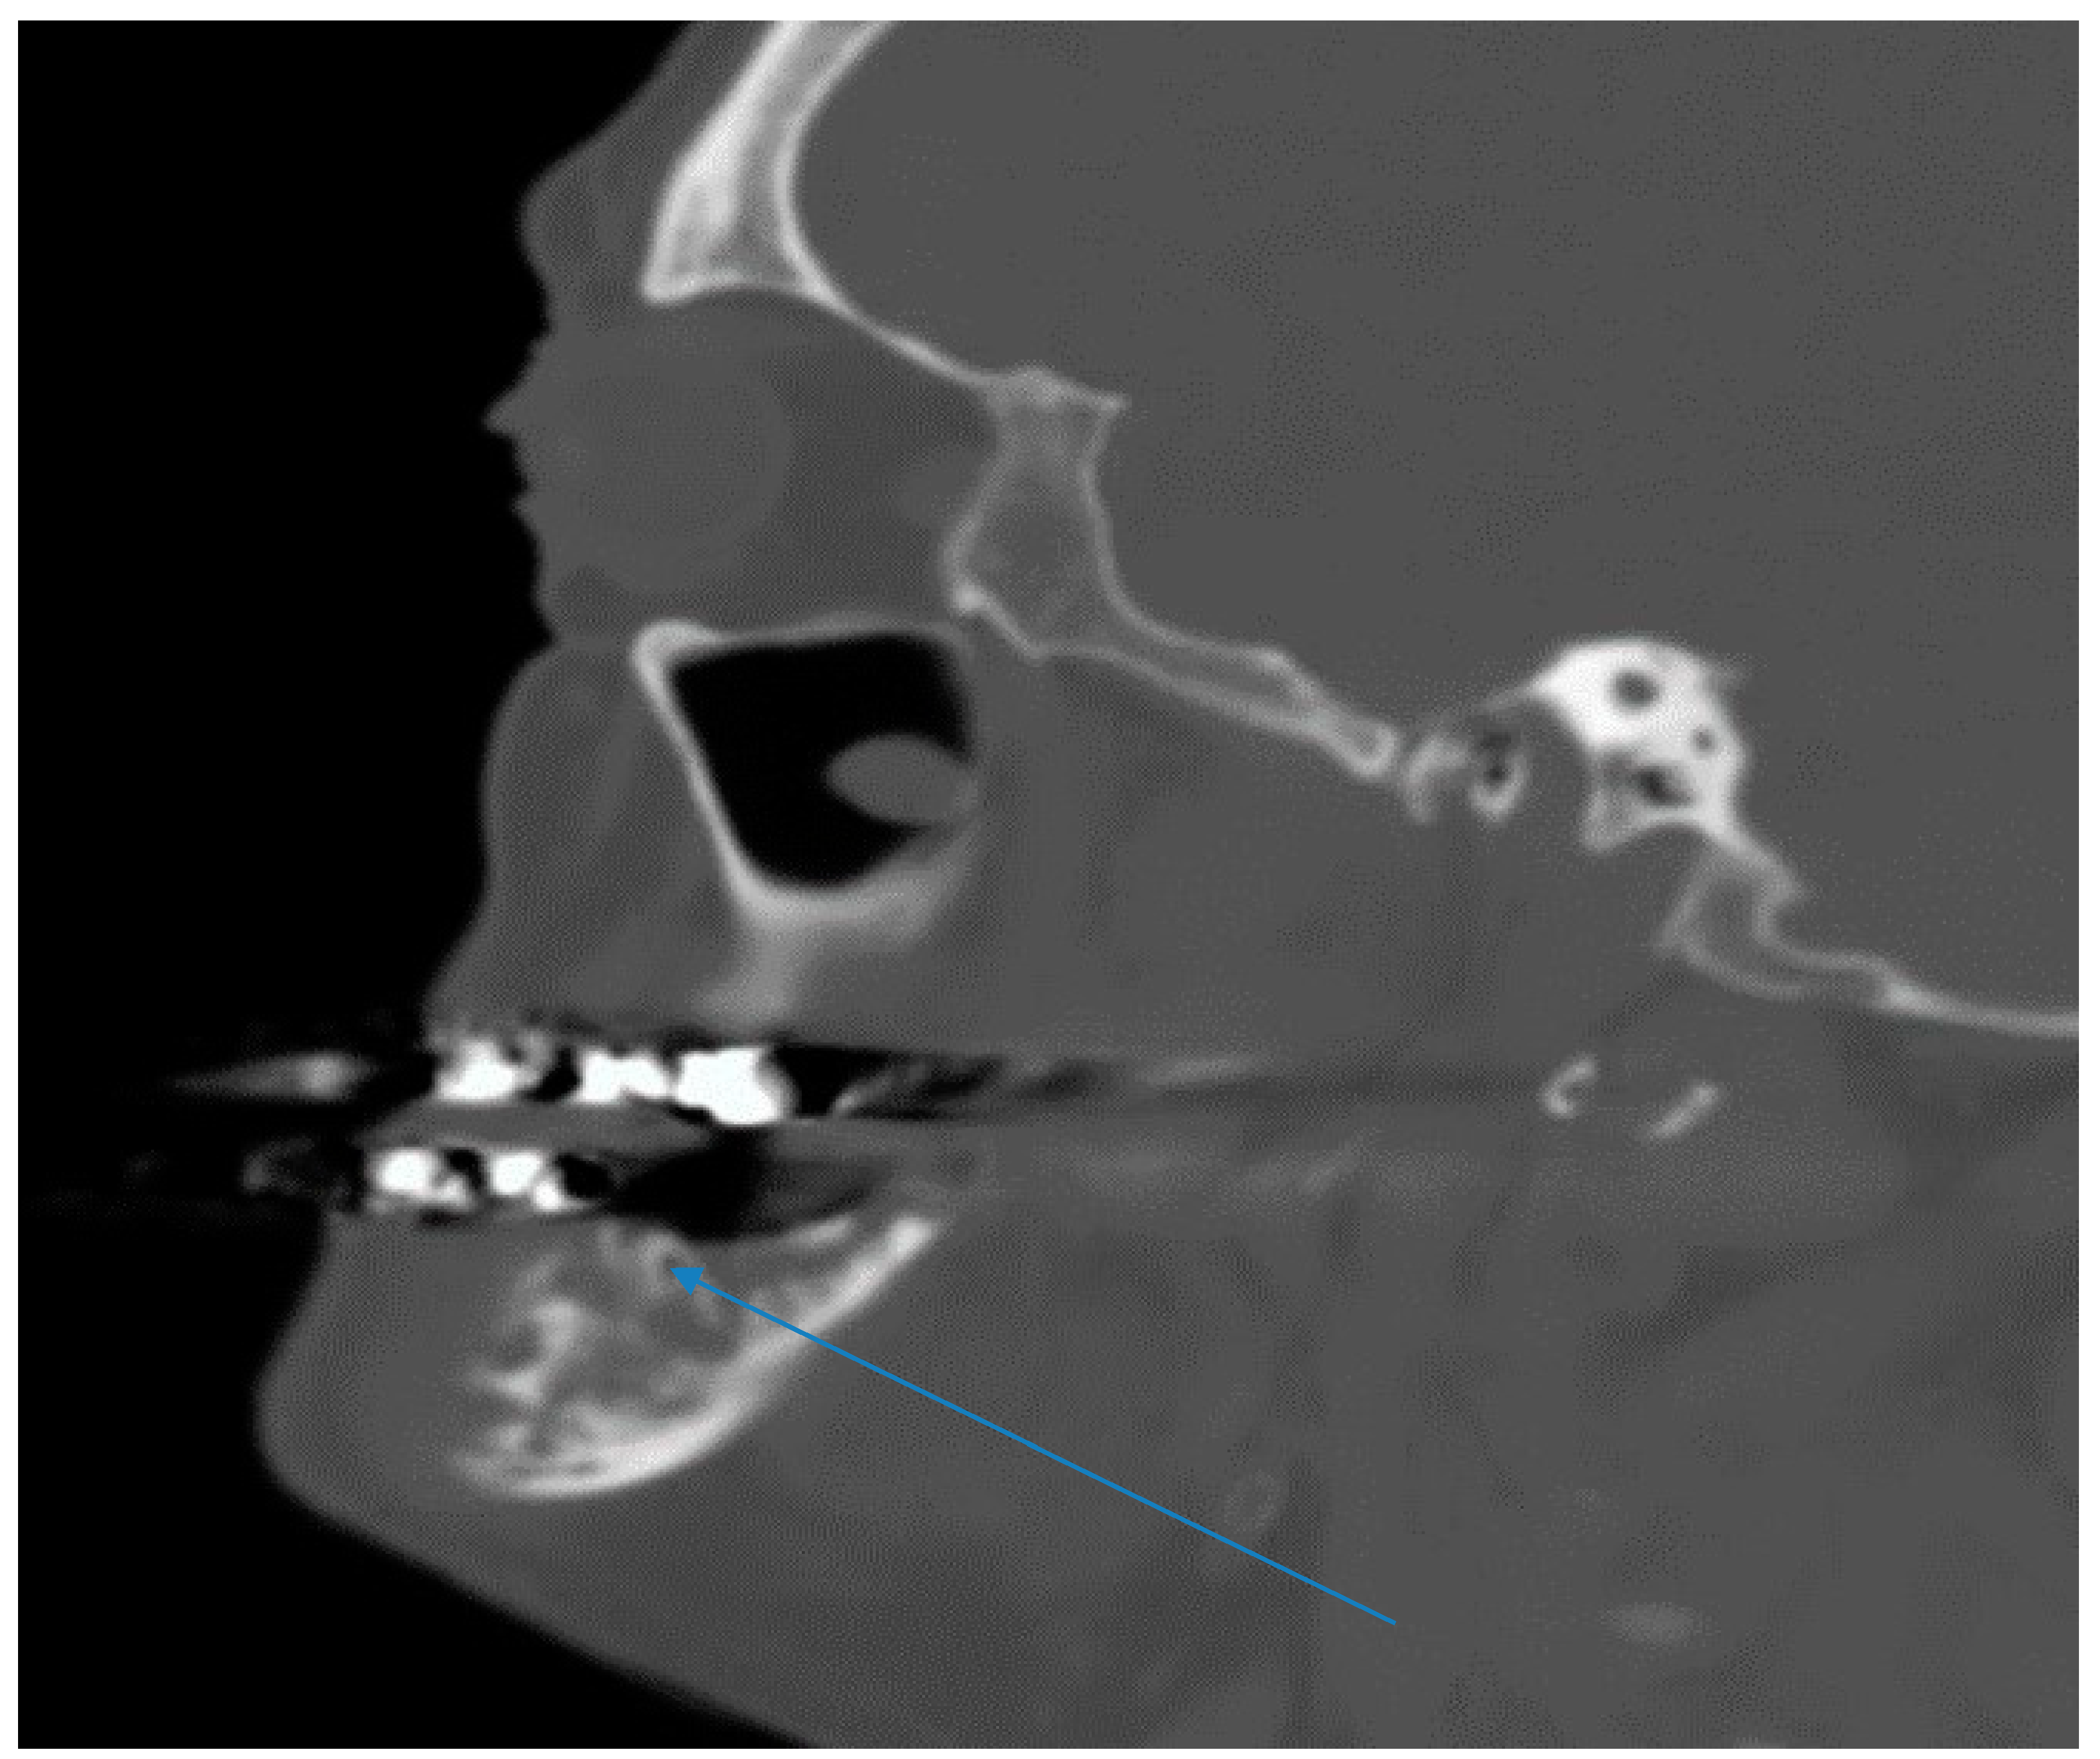

Computerized tomography maxillofacial imaging showed a lytic lesion in left ramus of the mandible with loss of bone matrix (Figure 2). Chest radiograph was completely normal. Differential diagnoses considered in addition to actinomycosis included nocardiosis, tuberculosis, osteosarcoma of the mandible and endemic fungal infections.

Figure 2.

Maxillofacial computerized tomography imaging showing a lytic lesion in left ramus of the mandible with loss of bone matrix (see arrow).